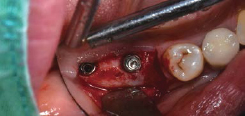

Single Implant

술전

발치

발치와

Volume Up Gauge를 Implant 식립부위에 위치하여 Healing Abutment 직경 확인

Volume Up Gauge의 홈에 맞춰 Point Drill의 위치 파악

제조사의 식립순서에 맞춰 Drilling 후 Fixture 식립

Fixture 식립

Volume Up Healing Abutment 체결

술후